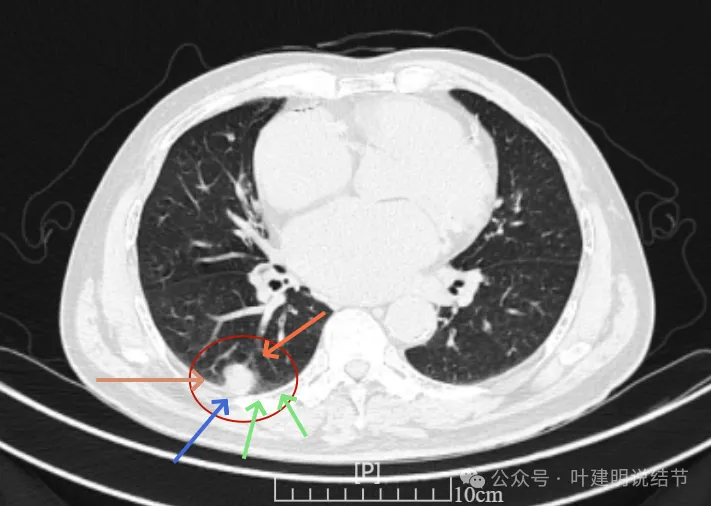

我们先来看2022年3月主要病灶的影像:

右上叶结节实性,密度高,边缘平整,轮廓清楚,像良性些。

右下似见微小结节,实性,与边上小血管截面不太好区分,过小没什么临床意义,能随访。

左下胸膜下实性结节,轮廓稍模糊,密度较高,边缘较光,像淋巴结些,能随访。